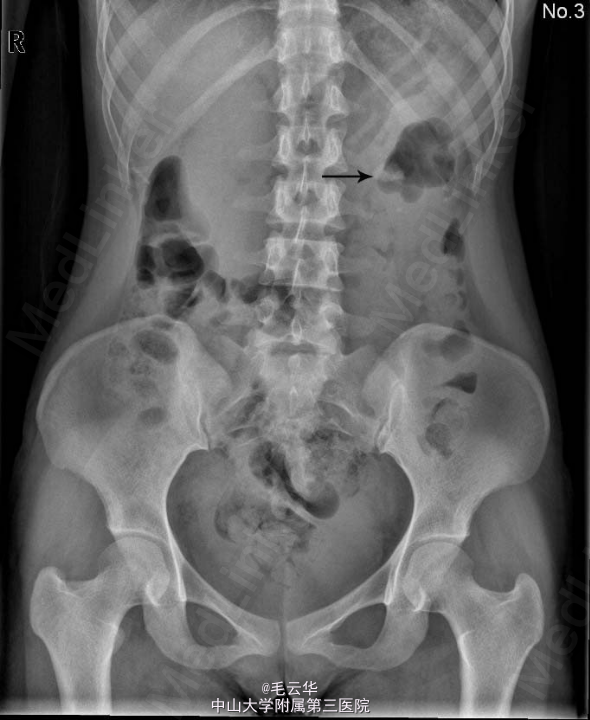

入院诊断:左肾结石 入院查尿常规RBC3003个/ul,KUB示左肾区平第2腰椎水平可见一结节状高密度影,大小为:17.8×9.9mm,考虑左肾结石。双肾CT平扫+增强+CTU示左肾下盏小结石;左侧盂管交界处结石(23×9mm),并左肾轻度积液。全麻下行左侧输尿管软镜碎石取石术,术程顺利,术后安返病房。